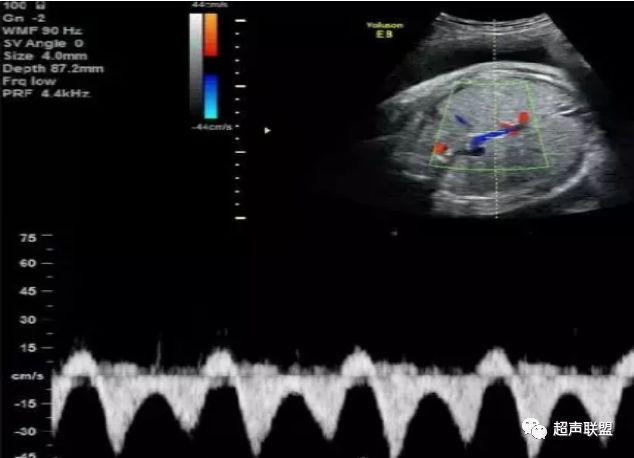

1 胎儿脐动脉测定

缺氧首先出现的变化是舒张末期血流降低,S/D值、RI值和PI值升高。当缺氧进入再分配晚期时,可逐渐出现舒张期血流减少、舒张期血流缺失。失代偿期出现脐动脉血液逆流,舒张期血流倒置。

2、脐动脉标准:孕30周后,S/D>3;晚孕期,RI >0.75;孕18~20周后,脐动脉舒张期缺如或反向(后者见于严重的宫内缺氧者);

图1 正常脐动脉血流频谱

图2 脐动脉舒张期血流消失或反向